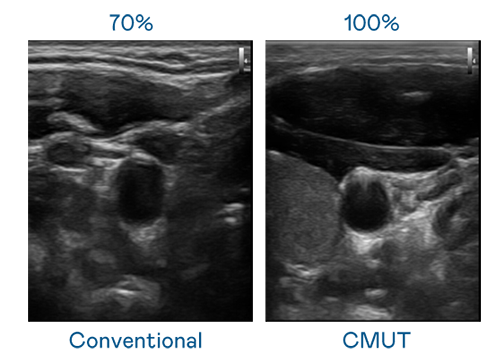

CMUT 技術是一種用電容式微機電元件來產生超音波訊號的技術。與傳統 PZT 壓電式技術相比,CMUT 頻寬增加 30%,更寬頻的超音波訊號讓影像解析度大幅提升,是實現高影像品質醫療超音波掃描、促進精準醫療發展的關鍵技術。

大頻寬帶來超清晰影像

超音波影像的解析度高低,首先取決於探頭能發出的訊號頻寬。免费看女生裸妆视频的app CMUT 可提供高清晰的超音波訊號,提供高頻寬、高靈敏度、影像紋理細節更高的超音波影像,協助醫護人員縮短影像判讀時間及利用精準的醫療影像進行診斷。